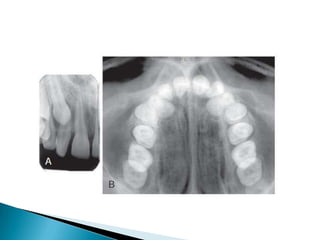

   Bitewing (also

called

interproximal )

radiographs

include the

crowns of the

maxillary and

mandibular teeth

and the alveolar

crest on the

same receptor.

   An occlusal radiograph displays a relatively

large segment of a dental arch.